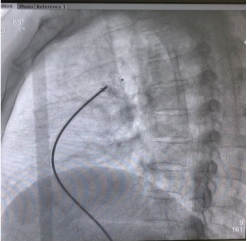

精准定位封堵器 成功释放封堵器

经过一系列精心准备,2021年4月30日,陈玺全主任带领石通主治医师在患者局麻、清醒的状态下,与超声诊断科罗开琴主任医师沟通配合,精准定位、精准手术,顺利完成了手术。